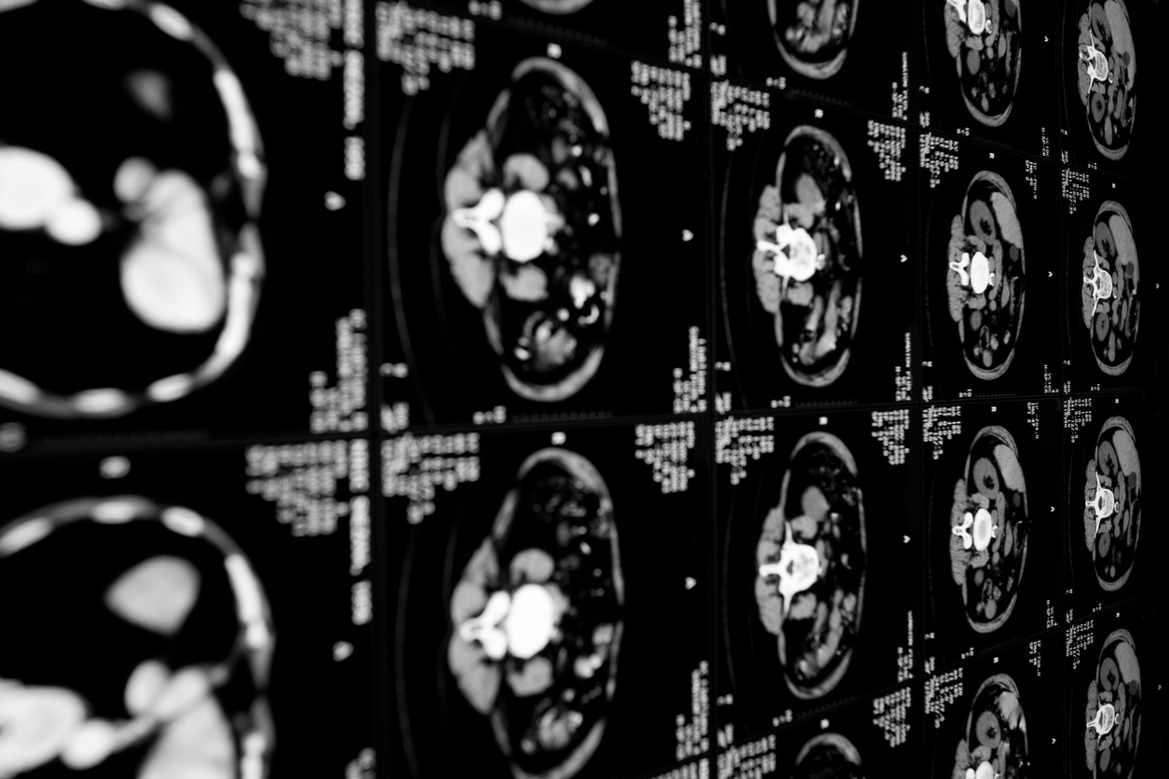

Des chercheurs suisses et canadiens ont découvert l’origine génétique d’un anévrisme cérébral particulier.

Appelée malformation artério-veineuse du cerveau, ou MAV, il s'agit d'une anomalie due à une mutation spécifique. Ce type d’anévrisme rare est une des principales causes d’hémorragies cérébrales chez le jeune adulte ou l’enfant.